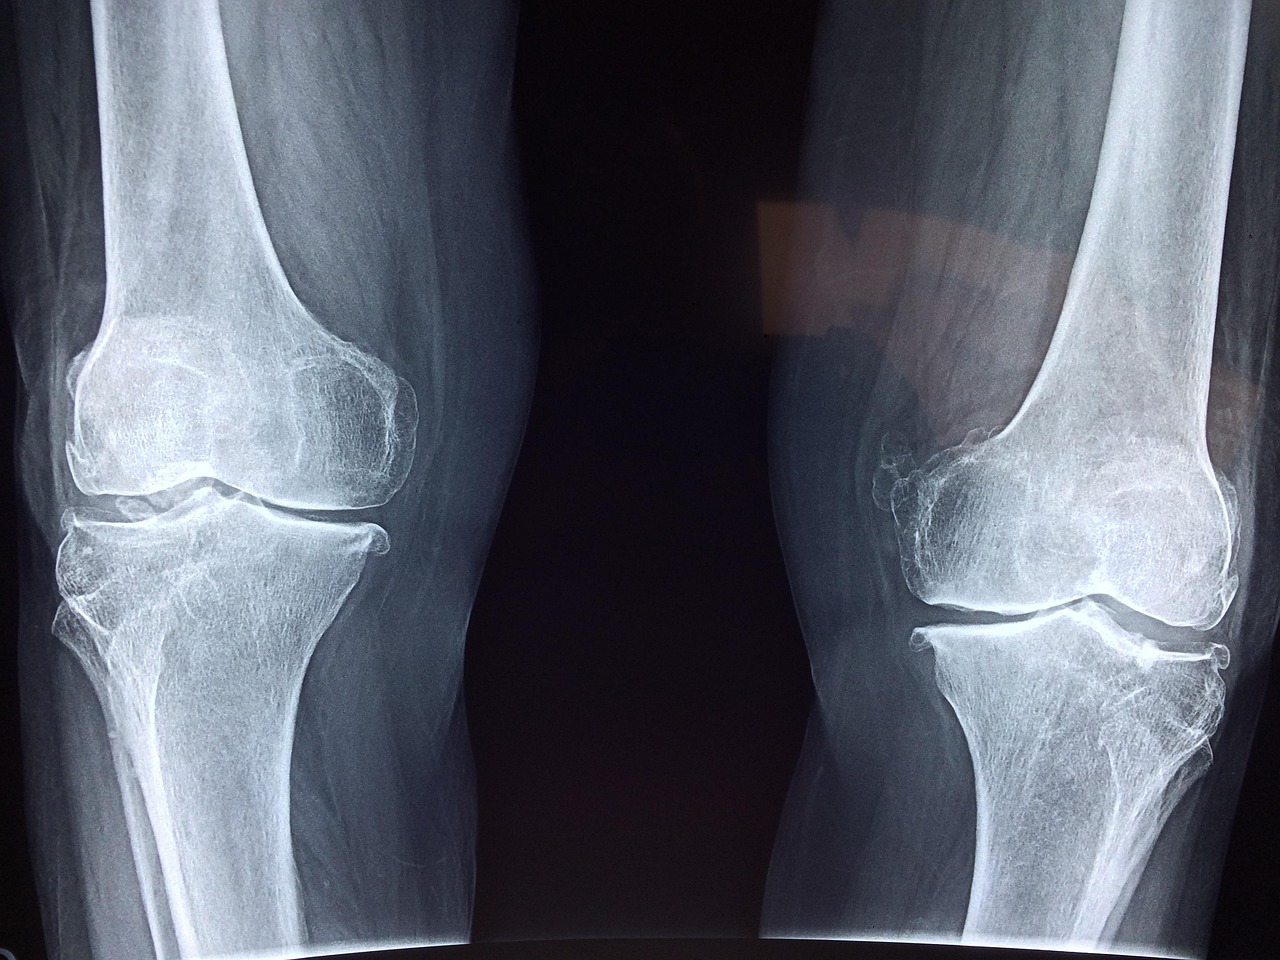

Several risk factors contribute to knee injuries, and recognizing them can guide preventive strategies. Age plays a significant role, as older individuals often face increased risks due to age-related wear and tear. Similarly, individuals with a previous history of knee injuries are at a higher risk of recurring issues. Furthermore, biological factors such as gender can influence risk; studies show that women are more prone to certain types of knee injuries compared to men. Another significant factor to consider is body weight. Excess body weight puts additional stress on the knee joints, raising the probability of injuries during activities. Additionally, overuse can lead to chronic conditions and acute injuries. Overtraining without appropriate rest disrupts the normal recovery process, making muscles fatigued and vulnerable. Training on different surfaces can also affect injury risk. Hard surfaces may increase the impact on knees during high-impact exercises, while uneven terrains can lead to falls and awkward landings. Another critical element is the choice of activities. High-impact exercises or sudden changes in intensity can stress the knees if not approached with caution. Understanding these risk factors allows individuals to tailor their fitness approach responsibly.